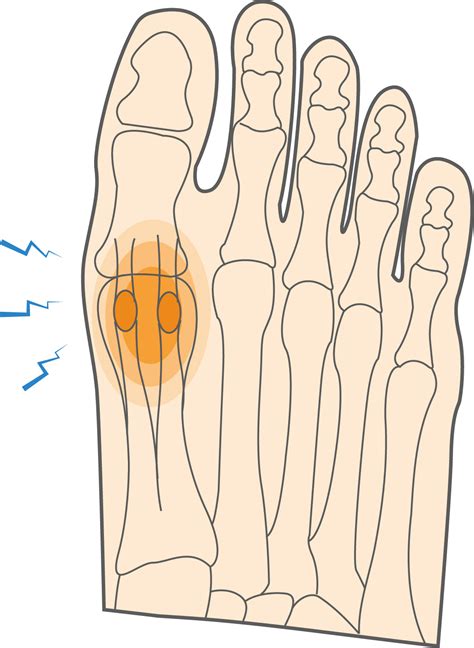

• Sesamoiditis: Inflammation of the two small, pea-shaped bones (sesamoids) embedded in the tendons beneath the big toe joint.